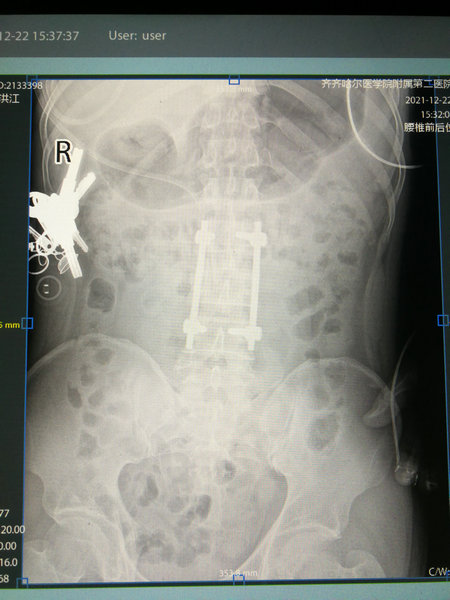

12月22日,一切准备就绪,陶先生如期进入手术室手术,在麻醉师的精准麻醉下,朱剑峰主任带领医疗团队按照既定手术方案历经1个半小时顺利完成了钉棒内固定术。

陶先生术后核磁影像

这个手术既能稳稳固定骨折的腰椎,同时对陶先生的创伤又降到了最低。术后第二天,陶先生的右下肢麻木感觉已有了明显缓解,双下肢肌力较术前也明显改善,这证明陶先生腰椎骨折已经得到了稳定固定,骨折对神经的压迫也得到了纠正。见到陶先生的病情迅速好转,病房的医护人员及家属都露出的欣慰笑容。